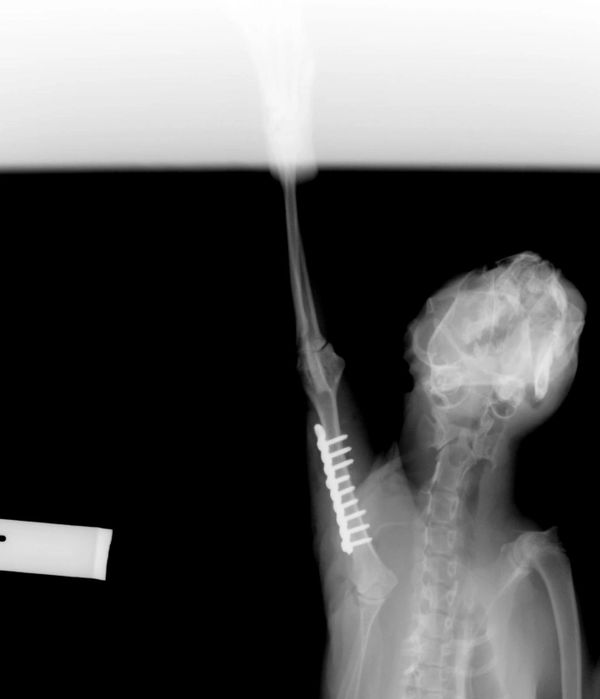

We rescued 'Soldier Boy' from the Pound recently and booked him in for Desex, Microchip and Vaccination.

During his consultation with the Vet, a nurse discovered that 'Soldier Boy' was unhappy about having his 'Left Shoulder/Leg' touched.

After further investigation under Anaesthetic... a Bullet was removed from his shoulder.

It appears that a heartless individual had shot at him.

We were absolutely mortified upon hearing this news... and unfortunately this isn't the first Bullet that Vets have removed from a cat we have rescued.